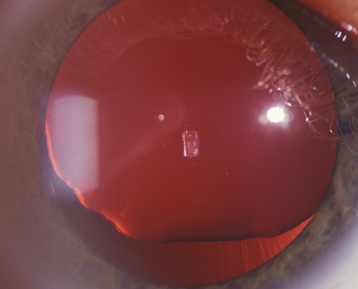

(See Figure 13.2.1.)

Lens dislocated into the anterior chamber.